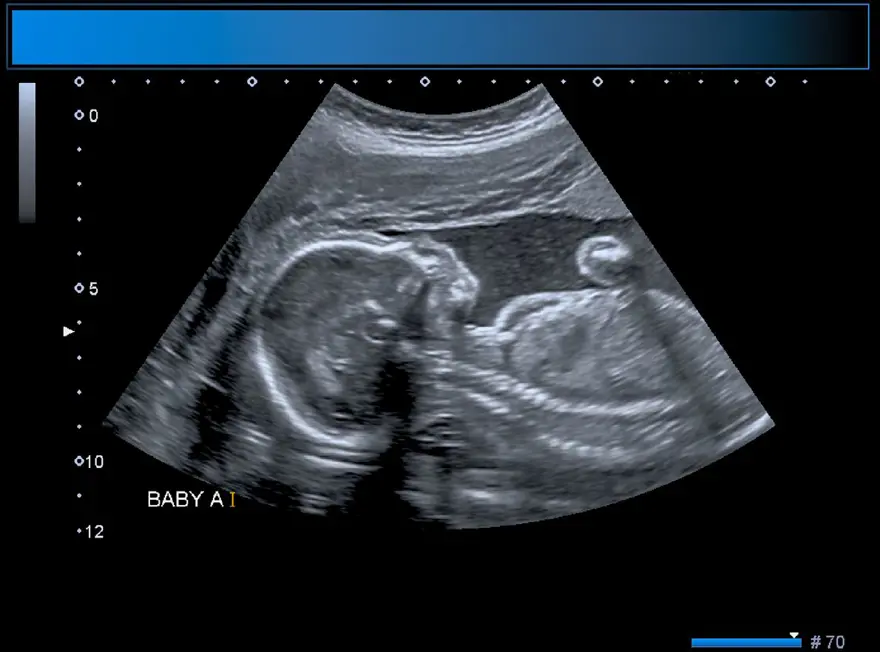

Çin'de doğmamış ikizinin fetüsü, bir yaşındaki kız bebeğin kafatasından ameliyatla çıkarıldı. 'Fetüs içinde fetüs' adı verilen oldukça nadir vakada, doktorlar fetüsün üst uzuvlarının, kemiklerinin ve hatta tırnaklarının gelişmiş olduğunu, yani kardeşinin içindeyken aylarca büyümeye devam ettiğini söyledi.Yaklaşık beş santim uzunluğundaki fetüs, ancak ebeveynler kızlarını kafası büyüdüğü ve motor becerilerinde sorunlar yaşadığı zaman doktora götürdüklerinde fark edildi.

Şangay'daki doktorlar, doğmamış ikizin fetüsünün çocuğun beyninde geliştiğini tespit etti. Çalışmanın yazarları, "Motor becerilerinde gecikmesi ve genişlemiş baş çevresi olan 1 yaşındaki bir kız çocuğunda malforme olmuş monokoryonik diamniyotik ikiz olan intraventriküler fetüs içinde fetüs (fetus-in-fetu) tespit edildi." denildi.